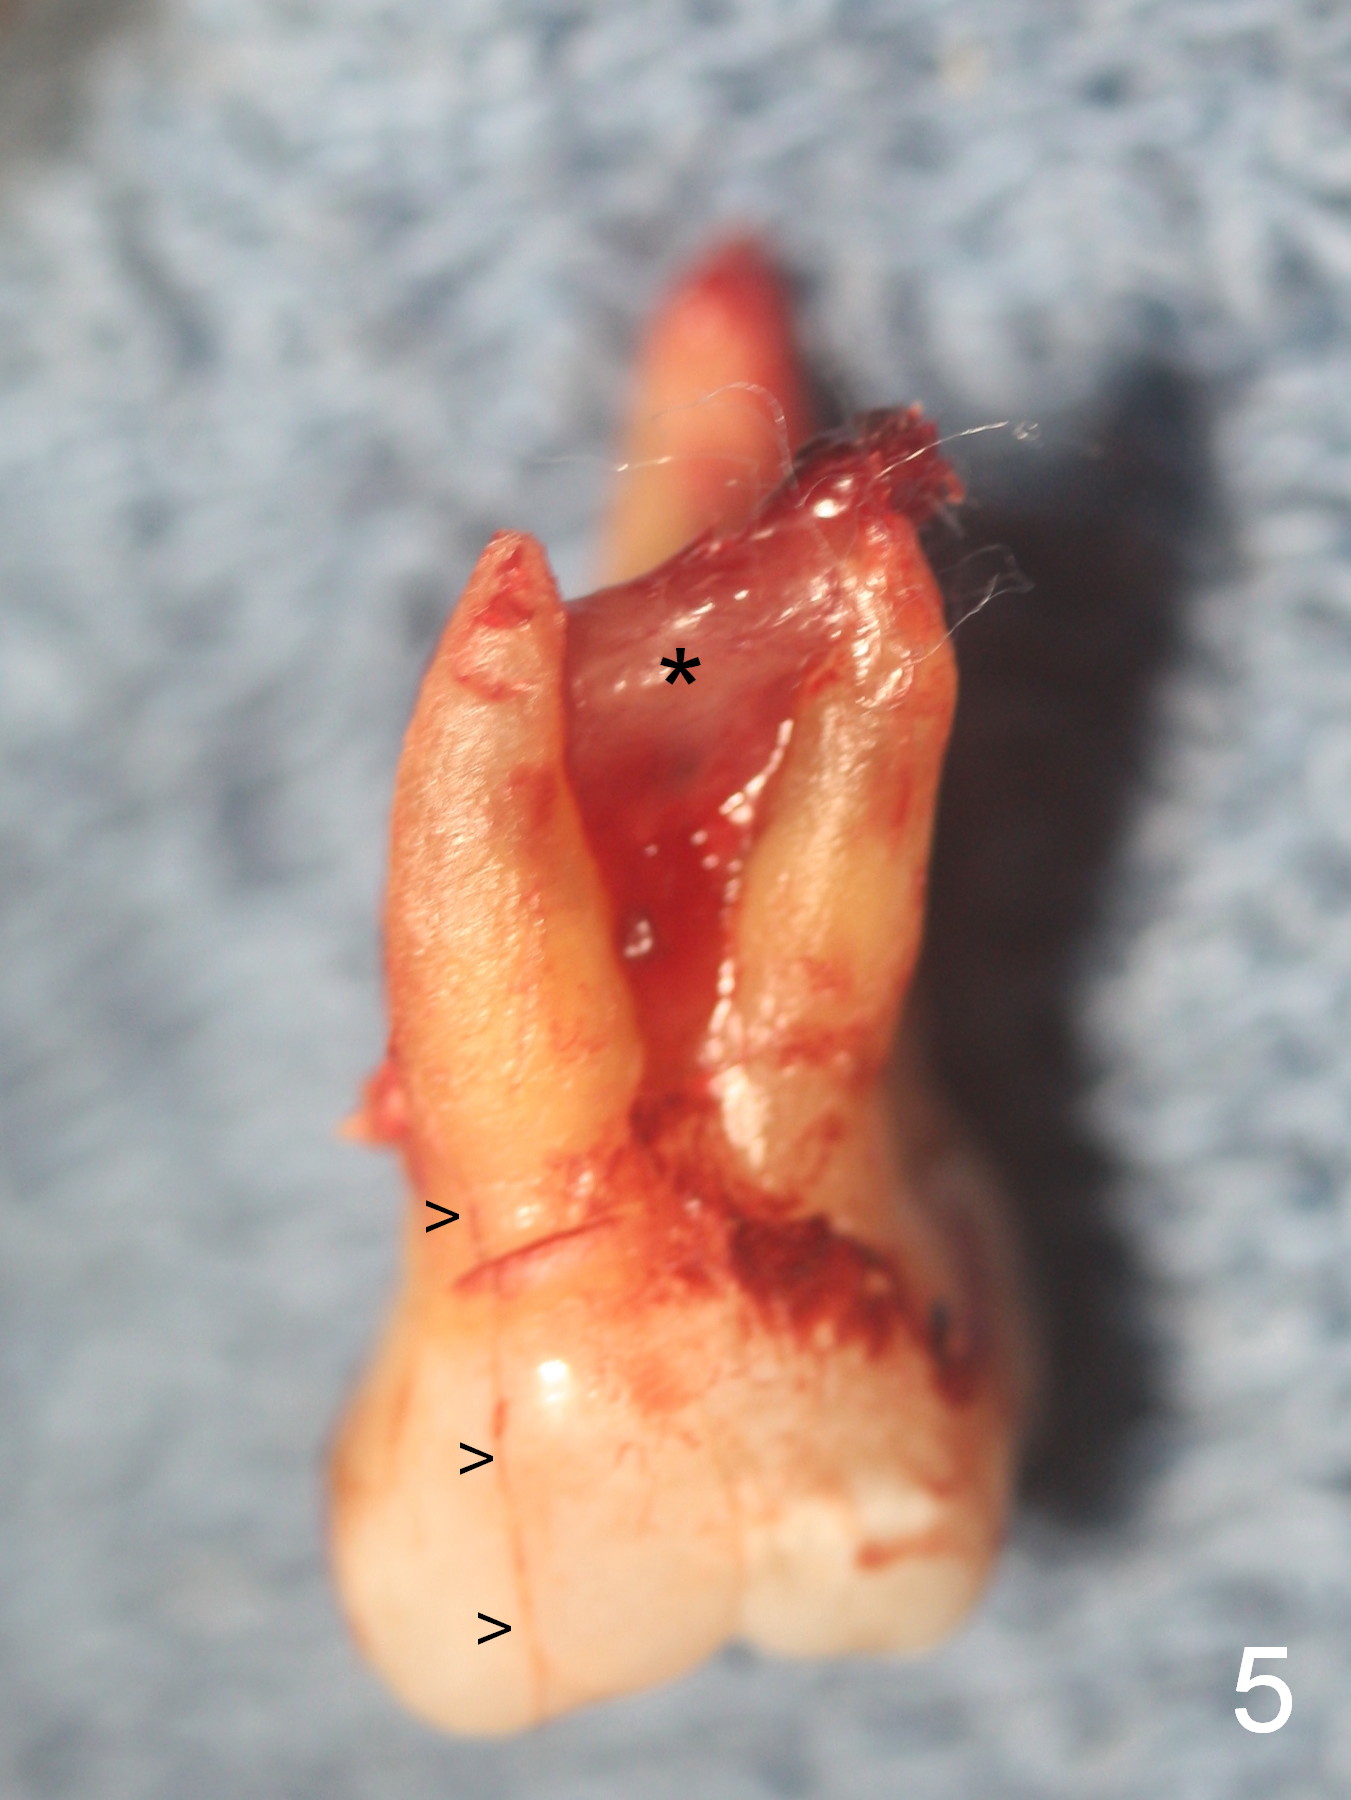

Extensive Crack Line

Approximately 2 months ago, the patient had vague pain in the upper left quadrant. The tooth #15 appeared to have crack tooth syndrome. Recently she developed severe pain and saw a periodontist. When she returns to our office, there is an obvious crack line lingually (Fig.1 <) with a nearby abscess (*). The crack line happens to be visible in X-ray (Fig.2 black <). The buccal abscess is larger (Fig.3 *); more surprising is hardly visible mesiobucal crack line (>).

When the tooth is extracted, the lingual crack line (Fig.4 white <) is contiguous with the mesiobuccal one (black >). The latter corresponds to the white arrowheads in Fig.2. In all the crack line is extensive. The buccal and palatal plates are defective coronally. The large granulation tissue in the furca (Fig.5 *) suggests bone loss in the crestal septum. Most surprising is a crack line in the distal surface of the tooth #13 (Fig.6 ^) and in the mesial surface of #15 (Fig.7). Night guard will be fabricated after an implant crown is cemented at #14.